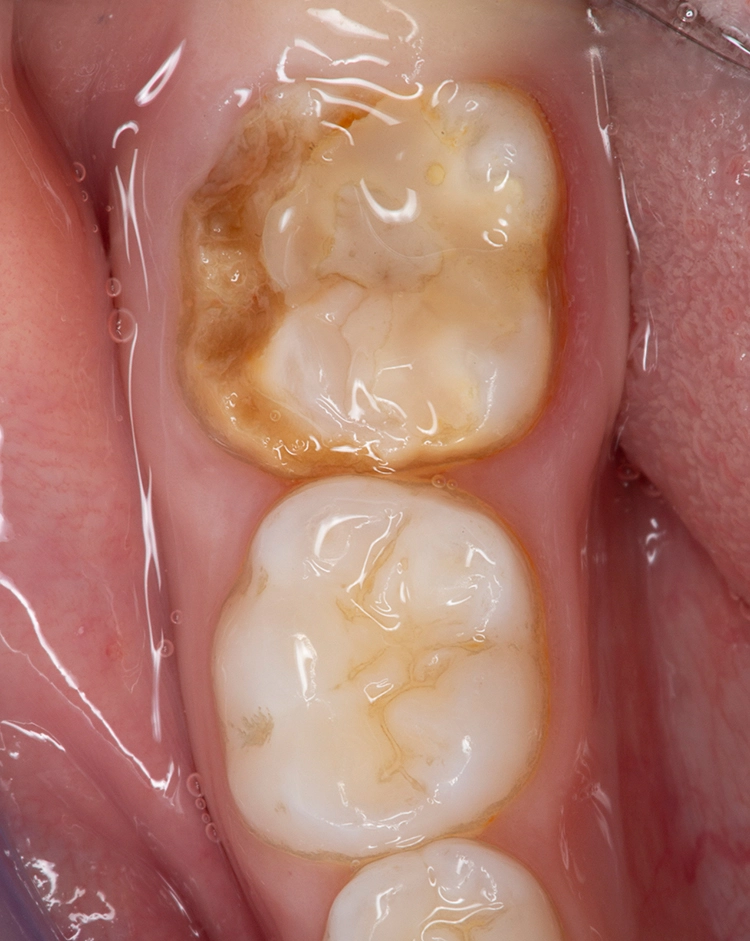

Die durch die Mindermineralisation bedingten Schmelzverluste sind meist ausgedehnt, sodass man eher selten auf approximale oder im Okklusalbereich begrenzte Kavitäten trifft, wie dies bei klassischen kariesbedingten Kavitäten oftmals der Fall ist. Bei ausgeprägten posteruptiven Abplatzungen kann es manchmal sogar zum Verlust ganzer Höckeranteile kommen (Abb. 3).

Bekes/BoukhobzaAbb. 3: MIH an Zahn 46. Typische Absplitterung des hypomineralisierten tragenden Höckers aufgrund der Kaubelastung.